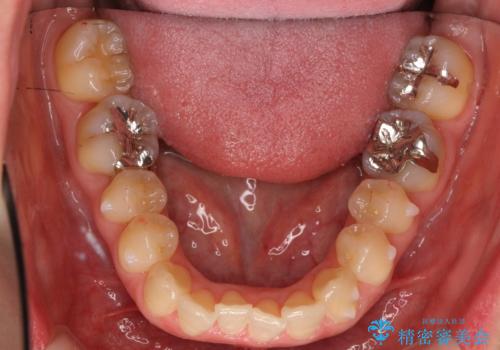

上の前歯が一部引っ込んでいる 下のがたがた マウスピース矯正

- 前歯2本が後ろに引っ込んでいる状態でした。

マウスピースで歯を抜かずに矯正しました。

かみしめがある方は、奥歯のかみ合わせが弱くなることがマウスピース矯正の欠点ですが、装着時間や時間帯を工夫して奥歯もしっかりかんだ状態で矯正終了をしています。